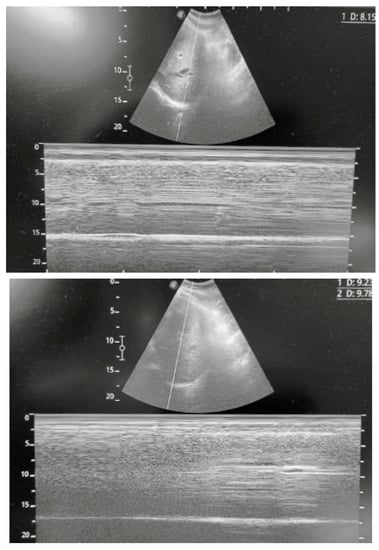

2. Diaphragm Function Assessment

3.1. Clinical Case One

3.2. Clinical Case Two